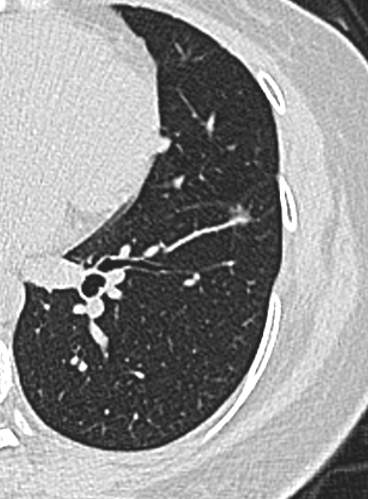

23年初复查CT左下肺GGO有所增大,直径:6.9mm

问题来了,一年多后复查GGO有增大,考虑恶性吗,需要手术吗,病理考虑什么?